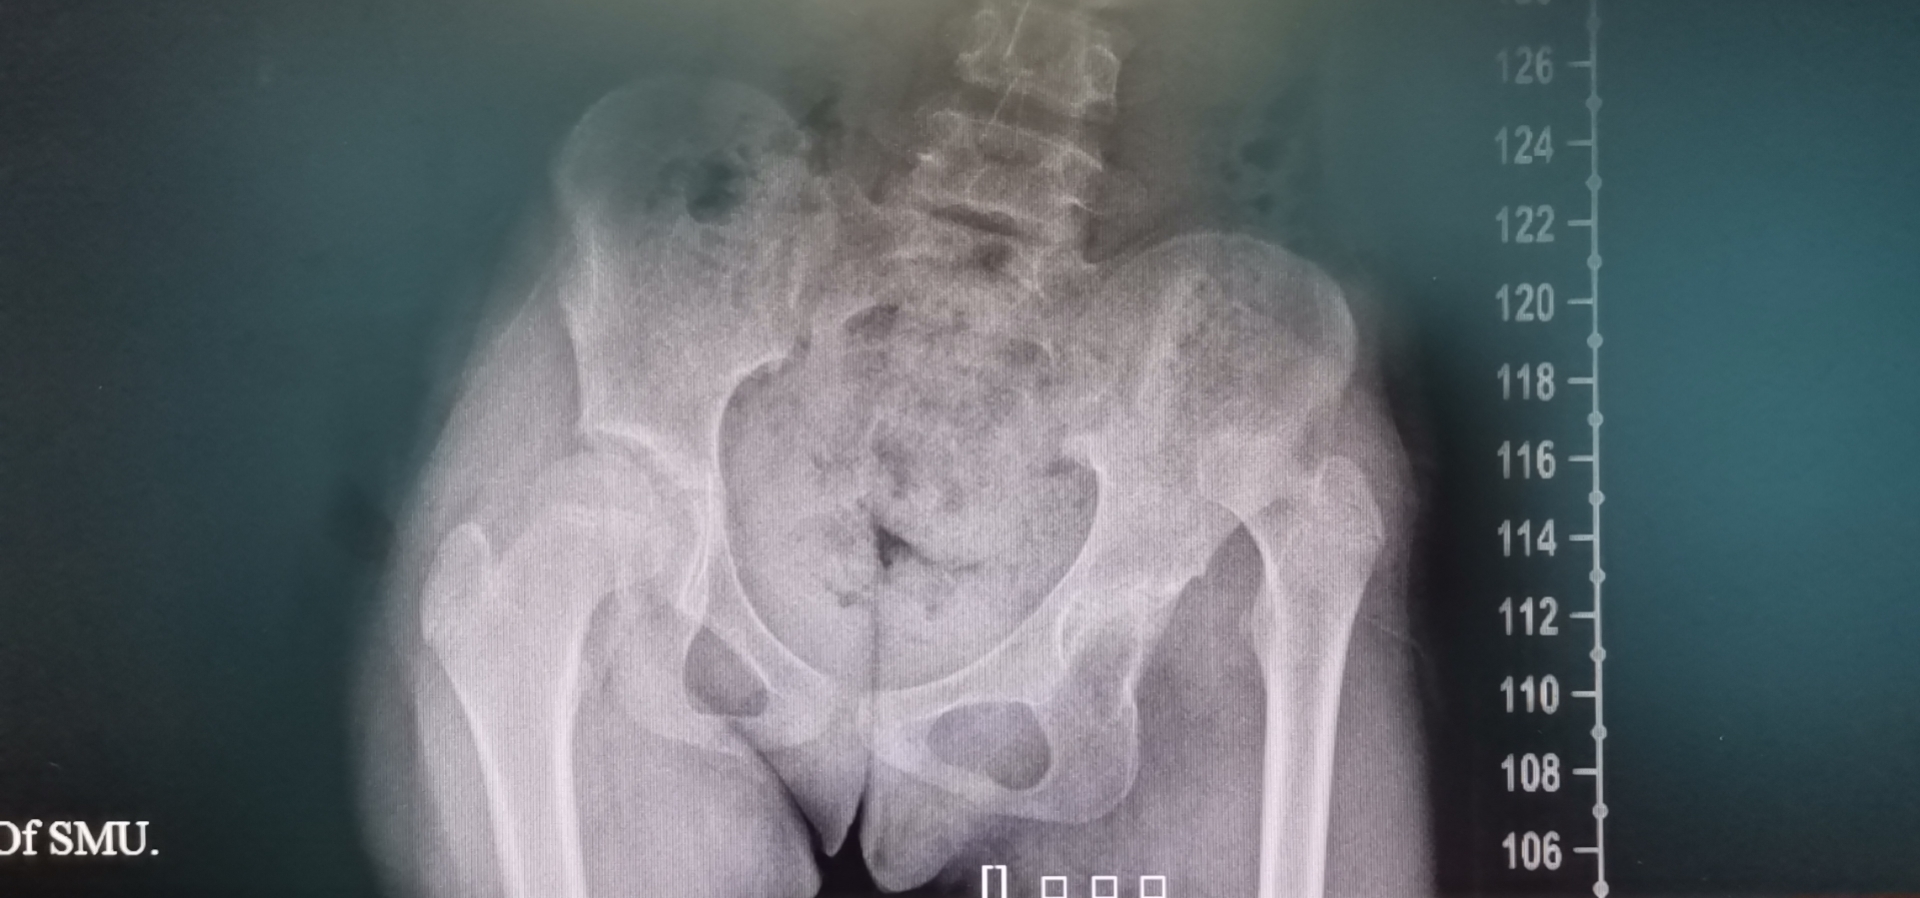

双侧髋关节脱位